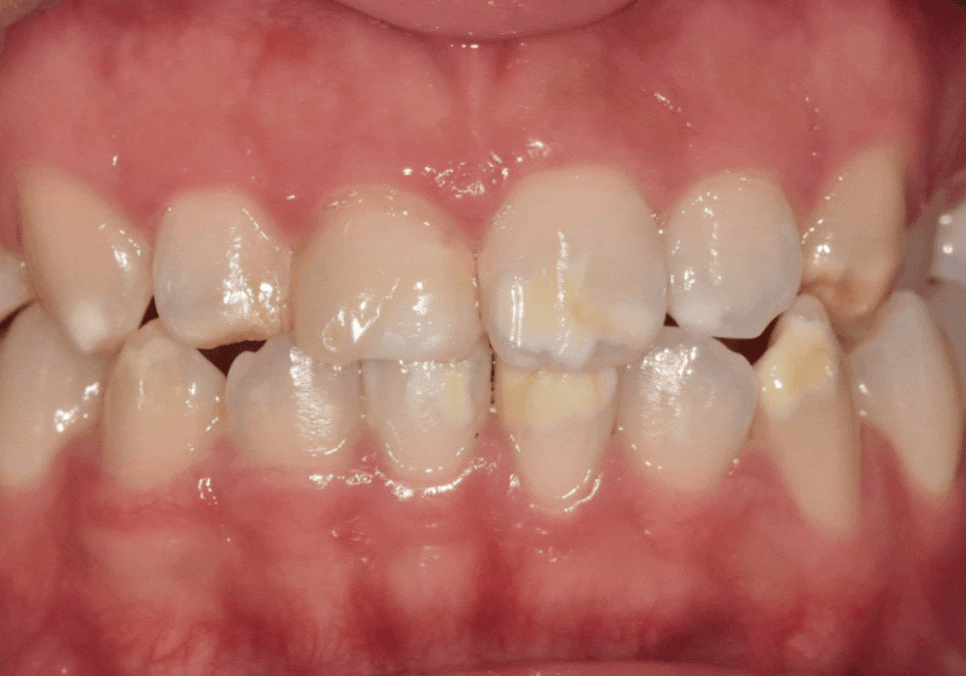

법랑질 형성 부전이나 불소 과다로 인한

흰 반점,갈색 반점이 있는 경우입니다.

앞니 변색, 치아미백효과 없는 이유

이 경우 미백을 하게 되면

반점 이외의 주변이 밝아져,

오히려 얼룩이 더 도드라져 보이기도 합니다.

그래서 미백보다는 라미네이트나 크라운 같은

보철 치료가 훨씬 효과적인 해결책이 됩니다.